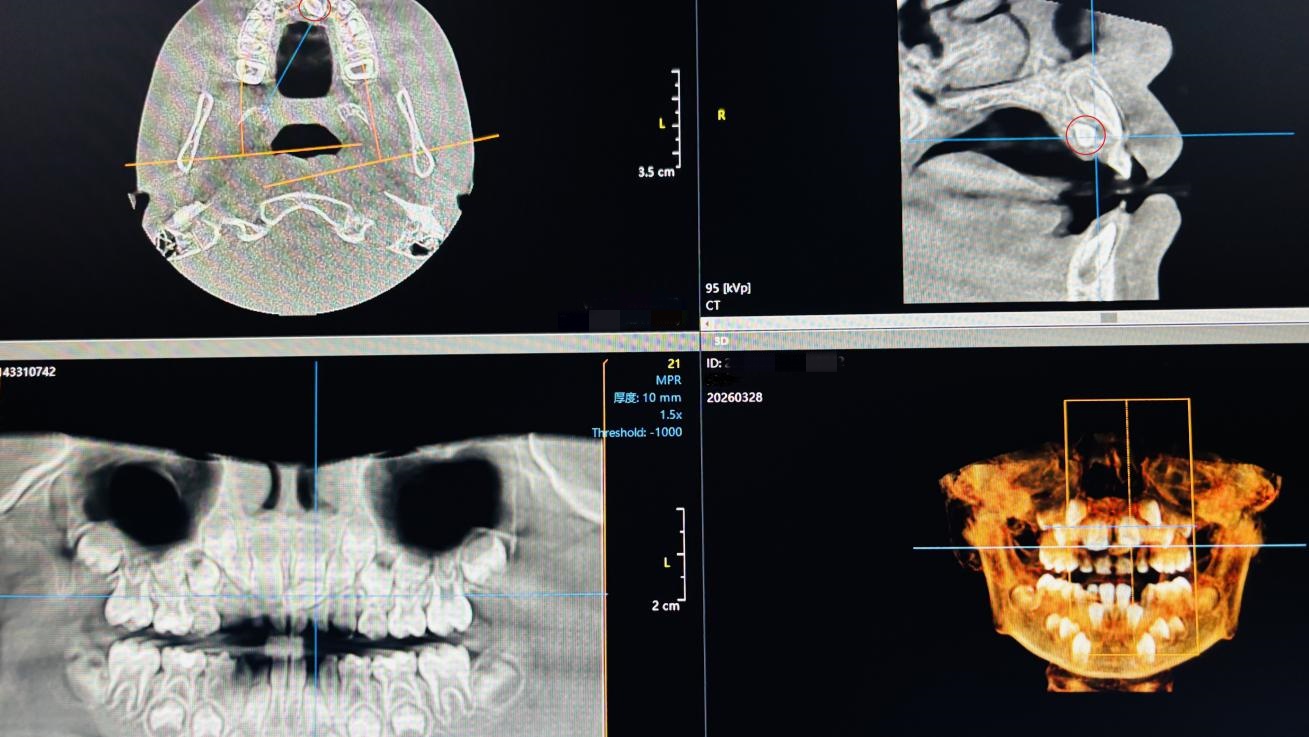

术前CBCT

医生经过细致检查,结合口腔CBCT(一种专门用于口腔颌面部检查的三维影像技术,通过旋转X射线束获取高分辨率立体图像,能清晰显示牙齿、颌骨及周围组织的细微结构),“病根”最终显露——在上颌前牙区的颌骨深处,“潜伏”着一颗多生牙。